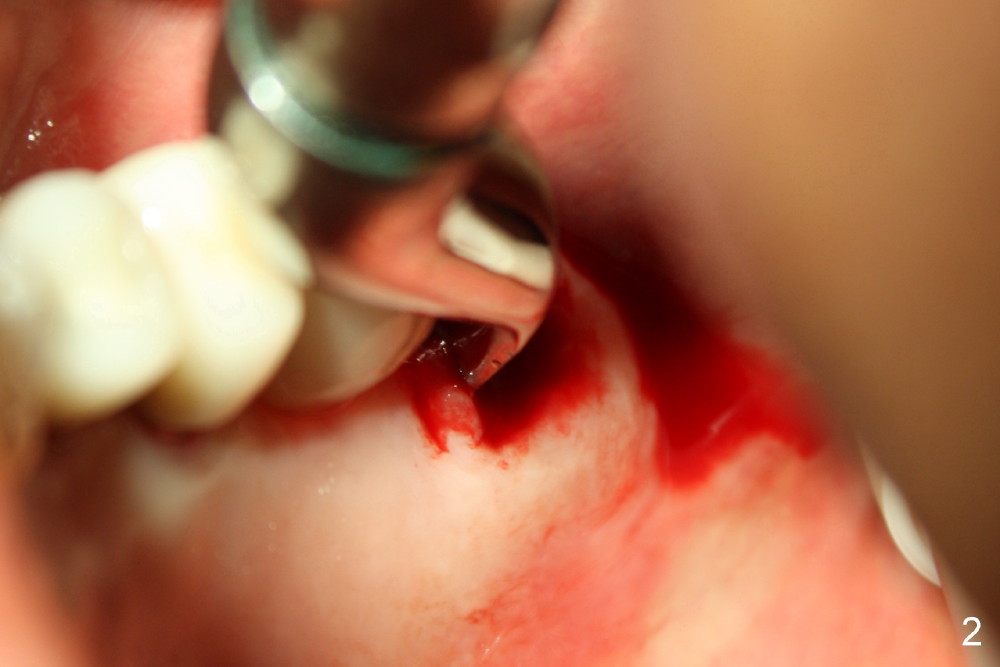

上颌磨牙有三个牙根,拔牙后一般有三个牙槽窝(图七(示意图)A:MB:近中颊侧;DB:远中颊侧;P:鄂侧),三个牙槽窝之间便是中隔(S)。如果中隔上面上颌窦不低,种植体应该种在中隔中。翁先生左上第二磨牙(图一:7)就与上颌窦无关,似乎后者不存在,前者牙根折裂,拔除后发现中隔鄂侧是一个斜坡,不容易插入圆骨凿或者钻头,所以用扁骨凿(图二)将中隔沿颊鄂侧劈开(图三),然后容易在中隔当中插入圆骨凿(图三插图白圆圈;图七B:蓝圆圈),由于中隔鄂侧阻力小,最后植牙(图七C:粉红色圆圈)不由自主地掉入鄂侧(图四),不得不移动颊侧粘骨膜瓣(图五B)关闭颊侧牙槽窝(图四插图(镜影观):MB;DB),图六镜影观(术后七天)显示种植体明显偏向鄂侧(P),可能造成以后修复困难。